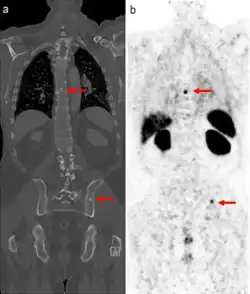

Medical images of a man's torso. Arrows indicate tumor metastases, visible as dots in the man's spine and pelvis, in both scans.

CT scan (left) and PSMA scan (right) showing prostate cancer metastases in the bone (red arrows). The dye used for PSMA scans is also absorbed by the kidneys, liver, and spleen (large dark objects at right).

The extent of cancer spread is assessed by MRI or PSMA scan – a positron emission tomography (PET) imaging technique where a radioactive label that binds the prostate protein prostate-specific membrane antigen is used to detect metastases distant from the prostate.[30][24] CT scans may also be used, but are less able to detect spread outside the prostate than MRI. Bone scintigraphy is used to test for spread of cancer to bones.[30]